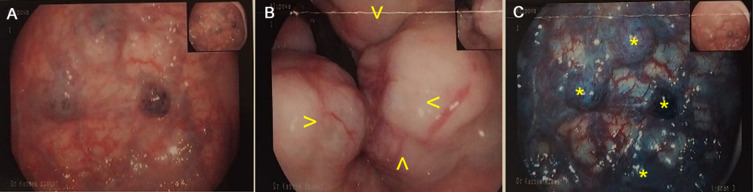

背景:直肠血管畸形与Klippel-Trenaunay综合征是非常罕见的。虽然他们的诊断可能是直截了当的特征,但由于其不寻常的表现和误诊的可能性,这些病例仍然具有重要的教育价值。病例介绍:我们的研究旨在描述一个45岁女性患者的临床病例。主诉有肛周疼痛,排便时/排便后周期性出血,痔疮脱垂,全身乏力。结肠镜检查显示直肠静脉曲张、直肠黏膜血管瘤和慢性内痔。对盆腔器官进行多层计算机断层扫描并静脉注射造影剂。临床初步诊断为直肠黏膜血管瘤,认为直肠血管畸形可手术。在我们的临床中,患者接受了几个阶段的手术:(1)在下腔静脉植入临时腔静脉过滤器,(2)两周后腹腔镜辅助直肠前切除术,预防性横结肠造口术和直肠粘膜脱粘术,(3)出院后7个月,关闭横结肠造口术。大体标本的病理检查显示,在切除远端延伸12.0 cm的部分,结肠粘膜致密,粗块状,颜色灰蓝色,有多个充血腔。术后进展顺利。第1天开始口腔营养和患者活动。术后创面初步愈合。患者于术后第6天顺利出院。结论:该病例定位罕见,病程长时间无症状,且有相当大的血管化过度的异常血管形成,值得关注。这种病理的合适方法是腹腔镜手术,这对于直肠血管畸形的诊断和根治性治疗都是有用的。

Case presentation: Our study aimed to describe a clinical case of a 45-year old female patient. There were complaints of pain in the perianal area and periodic bleeding during/after defecation, prolapse of hemorrhoids, general weakness. Colonoscopy revealed varicose veins of the rectum, hemangioma of the rectal mucosa, and chronic internal hemorrhoids. Multislice computed tomography of the pelvic organs with intravenous bolus contrast was performed. The preliminary clinical diagnosis was hemangioma of the rectal mucosa, and vascular malformation of the rectum was considered operable. In our clinic, the patient underwent several-stage surgery: (1) implantation of a temporary vena cava filter into the inferior vena cava, (2) two weeks later laparoscopic-assisted anterior resection of the rectum with preventive transverse colostomy and demucosation of the rectal mucosa, (3) after 7 months following discharge, the closure of transverse colostomy. Pathological examination of the gross specimen revealed that mucous membrane of the colon in a section extending 12.0 cm up to the distal edge of the resection is compacted, coarsely lumpy, grayish-bluish in color, with multiple blood-filled cavities. The postoperative period proceeded smoothly. Oral nutrition and patient's activity began on the 1st day. Primary healing of postoperative wounds was occurred. The patient was discharged in satisfactory condition on the 6th day post-surgery.